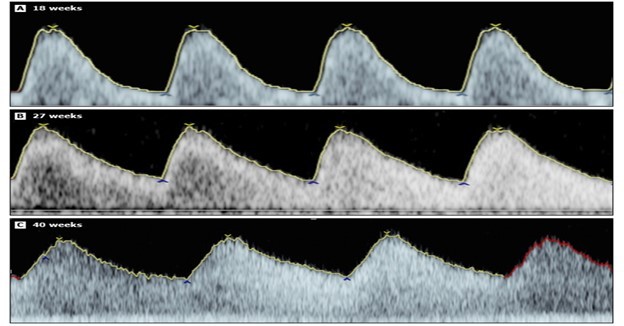

Fig. 1 Umbilical artery Doppler waveform in advancing gestational age in normal foetus. Note the diastolic flow increases with the gestational age.

Middle cerebral artery pulsatility index (fig. 3): In uncomplicated pregnancies, vascular resistance of the foetal brain changes with advancing gestation, thus the middle cerebral artery (MCA) PI is low at early gestational ages (<20 weeks), then gradually increases, before gradually decreasing in the third trimester [7]. However, in foetuses such as those with FGR experiencing progressive hypoxemia, cerebral blood flow increases to compensate for the decrease in available oxygen (brain-sparing effect), which results in a reduction in MCA PI. Subsequent normalisation of the MCA PI may occur and is considered an ominous sign because it indicates the loss of brain-sparing.